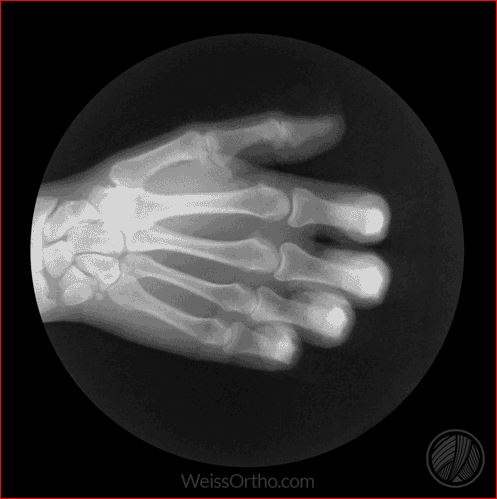

Met X-rays of Röntgenstralen kunnen we in ons lichaam kijken, maar we kennen het meestal gewoon als een foto: een stilstaand beeld van botten of gewrichten. Door fluoroscopie kunnen echter ook bewegende beelden gemaakt worden.

Ontwerper en fotograaf Cameron Drake ging aan de slag met beelden van het orthopedisch instituut van Dr. Noah Weiss in de V.S. (Weis Orthopaedics). Op zijn blog legt Drake uit hoe hij de beelden die Dr. Weiss gemaakt heeft van zijn patiënten omgezet heeft in deze gifs.

Zou ook heel interessant zijn om zo’n reeks te zien van gewrichten die aangetast zijn door Spondylitis Ankylosans (ziekte van Bechterew).